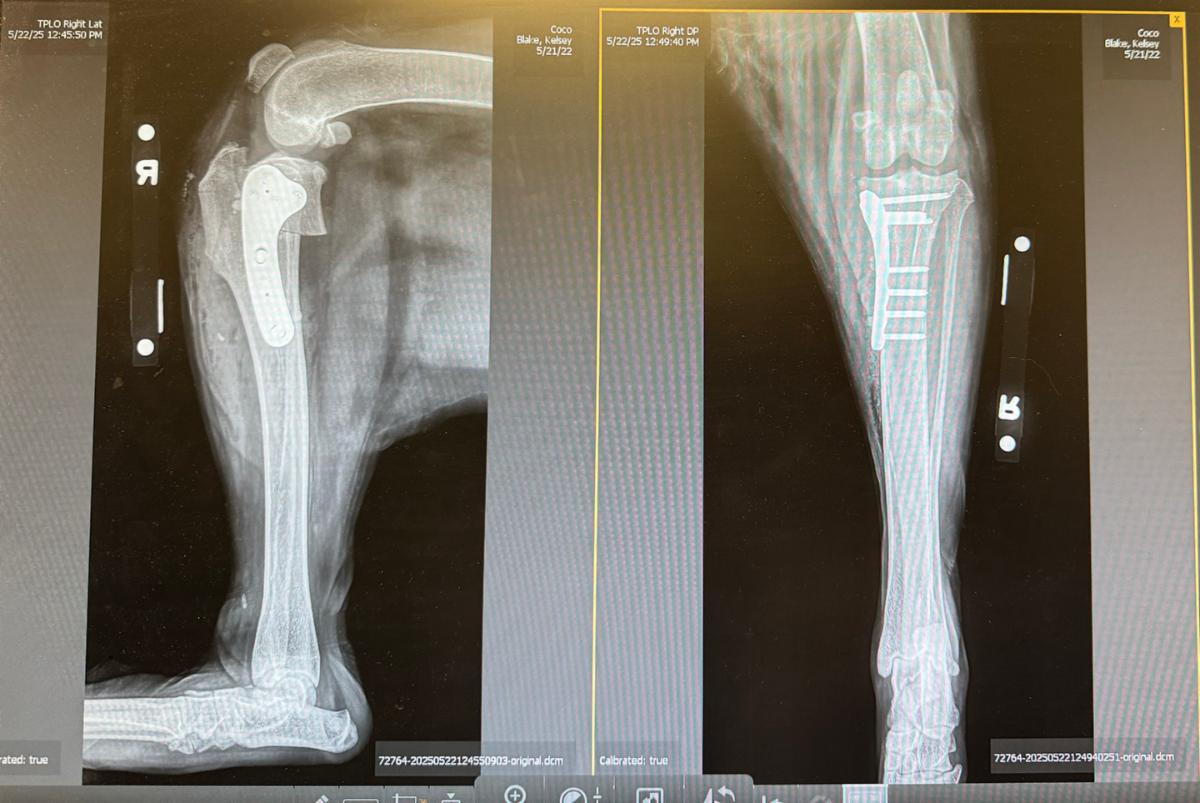

“Coco” had already been privately rehomed once in the Seattle area. Her new family had covered her spay expense and was managing veterinary ongoing costs due to megaesophagus. She recently sustained a torn cranial cruciate ligament that required surgical repair.  The Blake family applied and the Trust’s review process approved the grant.  Although other surgical services were available, the family chose to drive eight hours to the veterinary specialists in Idaho as recommended by Seattle club members.

Post-surgery the family reports, “She is doing well! Just keeping her down is the hardest part. She's already getting around really well.”